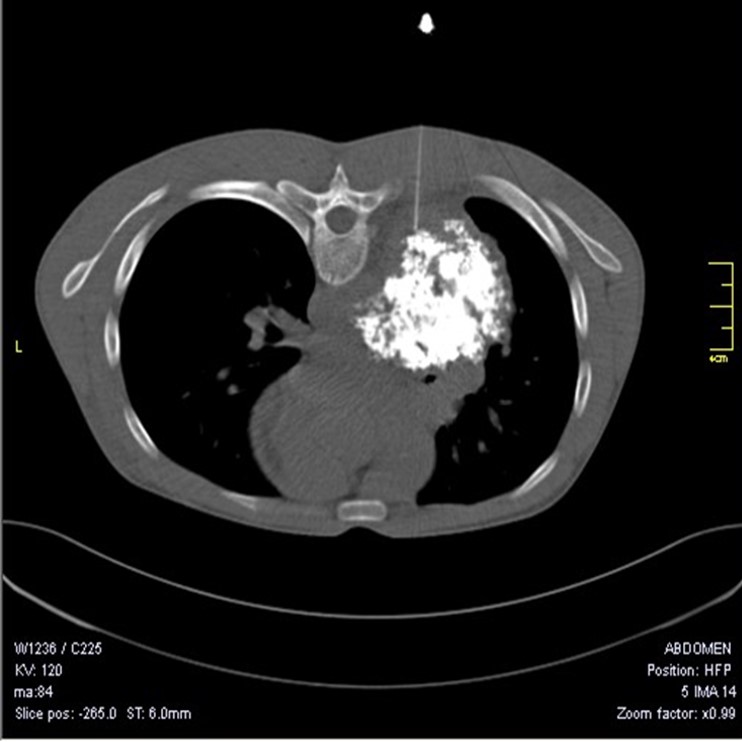

Introduction - Pulmonary hamartoma, with incidence of 0.25-0.32%, accounts for 6% of solitary pulmonary nodules. The role of radiology is limited as only 10-30% of cases show characteristic ‘popcorn’ calcification and Computed Tomography can detect approximately  50% of hamartomas. Hence cytological and/or histopathological examination is required to make a definitive diagnosis and exclude malignancy.

Observations – The age of the patients ranged from 17-63 years (mean-46.3), with male to female ratio being 3.5:1. The size of the hamartoma varied from 0.4 – 1.3 cm, with mean diameter of 1 cm. Cytology showed mixture of bronchial epithelial cells, adipocytes and stromal fragments in fibromyxoid and chondroid background. Histopathology demonstrated lobules of cartilage and adipose tissue with intervening clefts lined by respiratory epithelium and mesenchymal stroma.